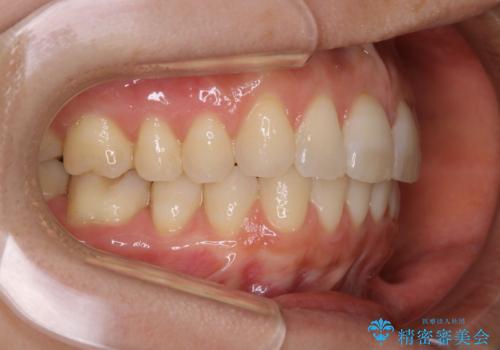

インビザラインFULLで奥歯の噛み合わせから改善させることで、上下の真ん中位置をしっかり合わせることが出来ました。

横顔のシルエットも改善させることができ、大変喜んでいただけました。